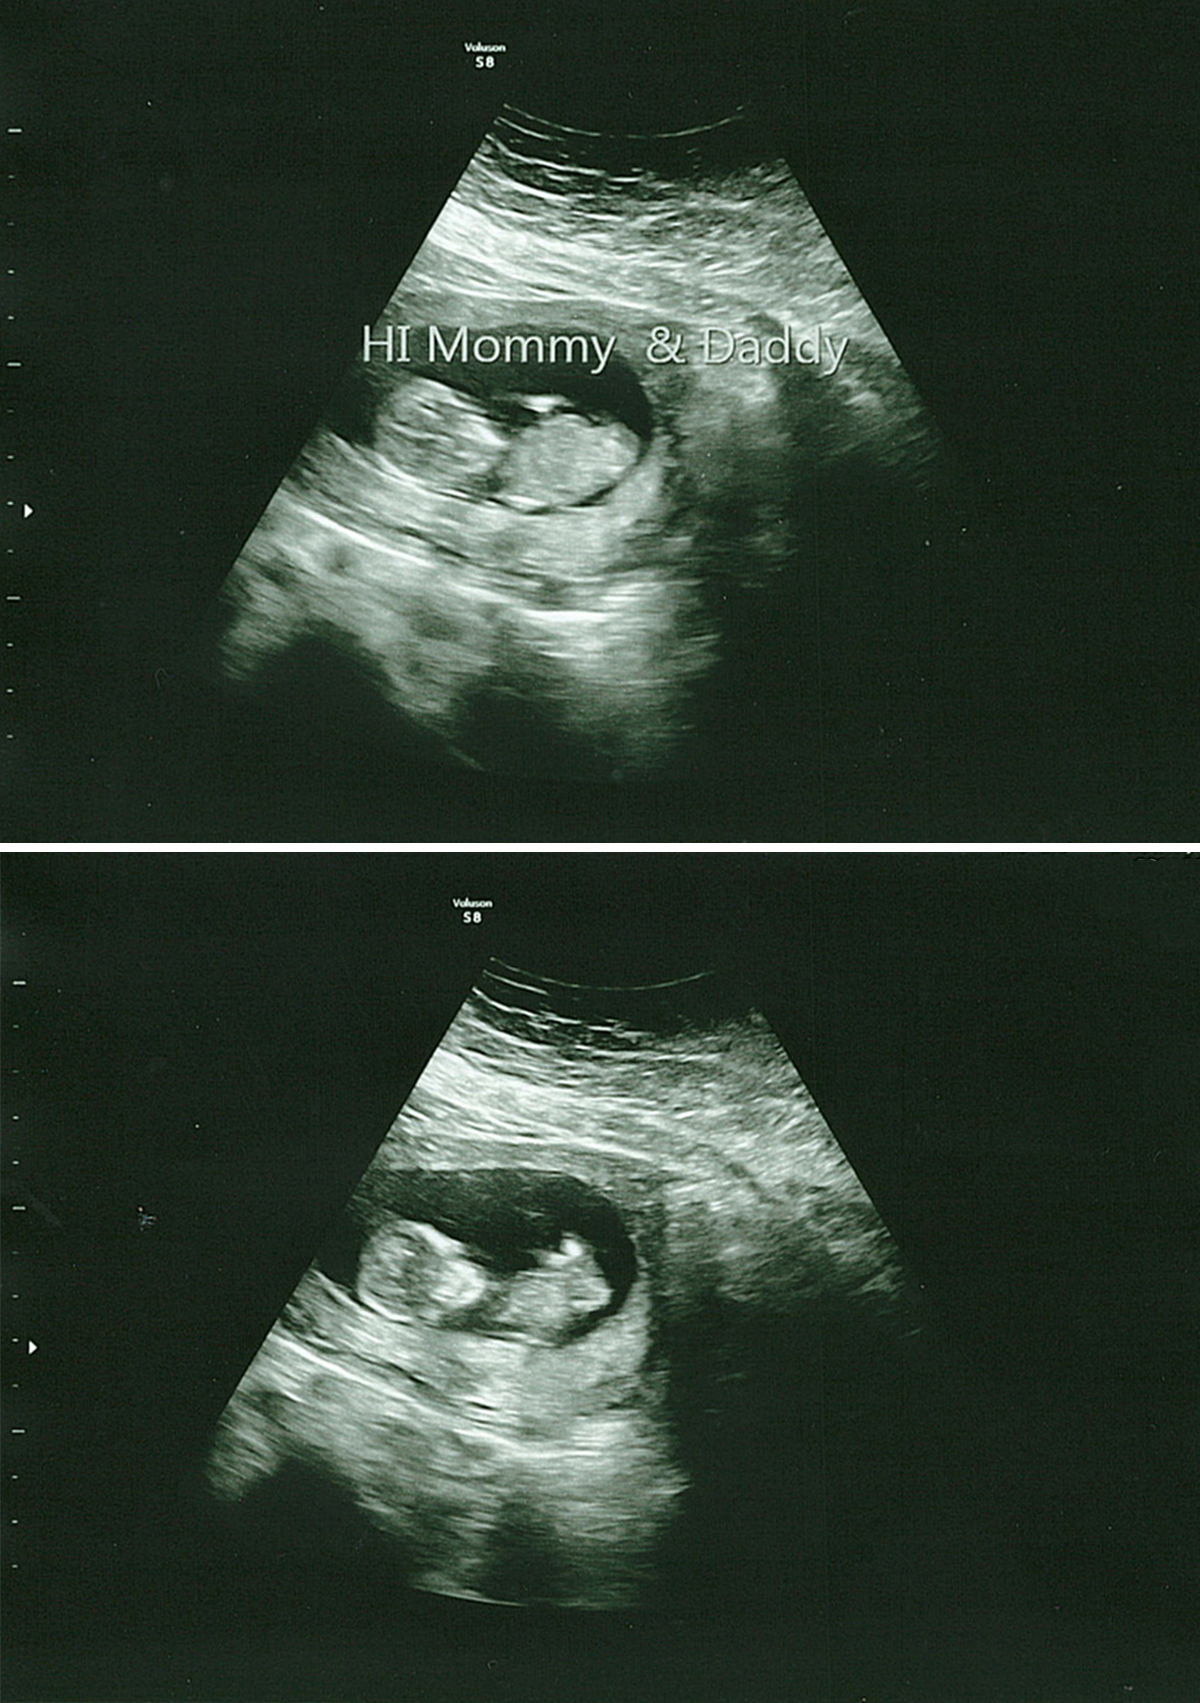

I’m happy to report the visit went amazing, and we couldn’t have asked for a better ultrasound tech. She first let us hear the heartbeat and even spent extra time with us, trying to get better photos (though I need to drink more water). She let us record the visit, and I’ve included a few pictures and a short video clip showing our baby moving around. Life is such a miracle, and seeing this baby, the size of a lime, move around was incredible.

This pregnancy – Video Clip from Our 12 Week Ultrasound

Here’s a short clip from our visit where you can see our baby moving around. This visit was exactly what we needed, and I feel even more connected to this little human, though it’s still crazy to think they’re growing inside my body.